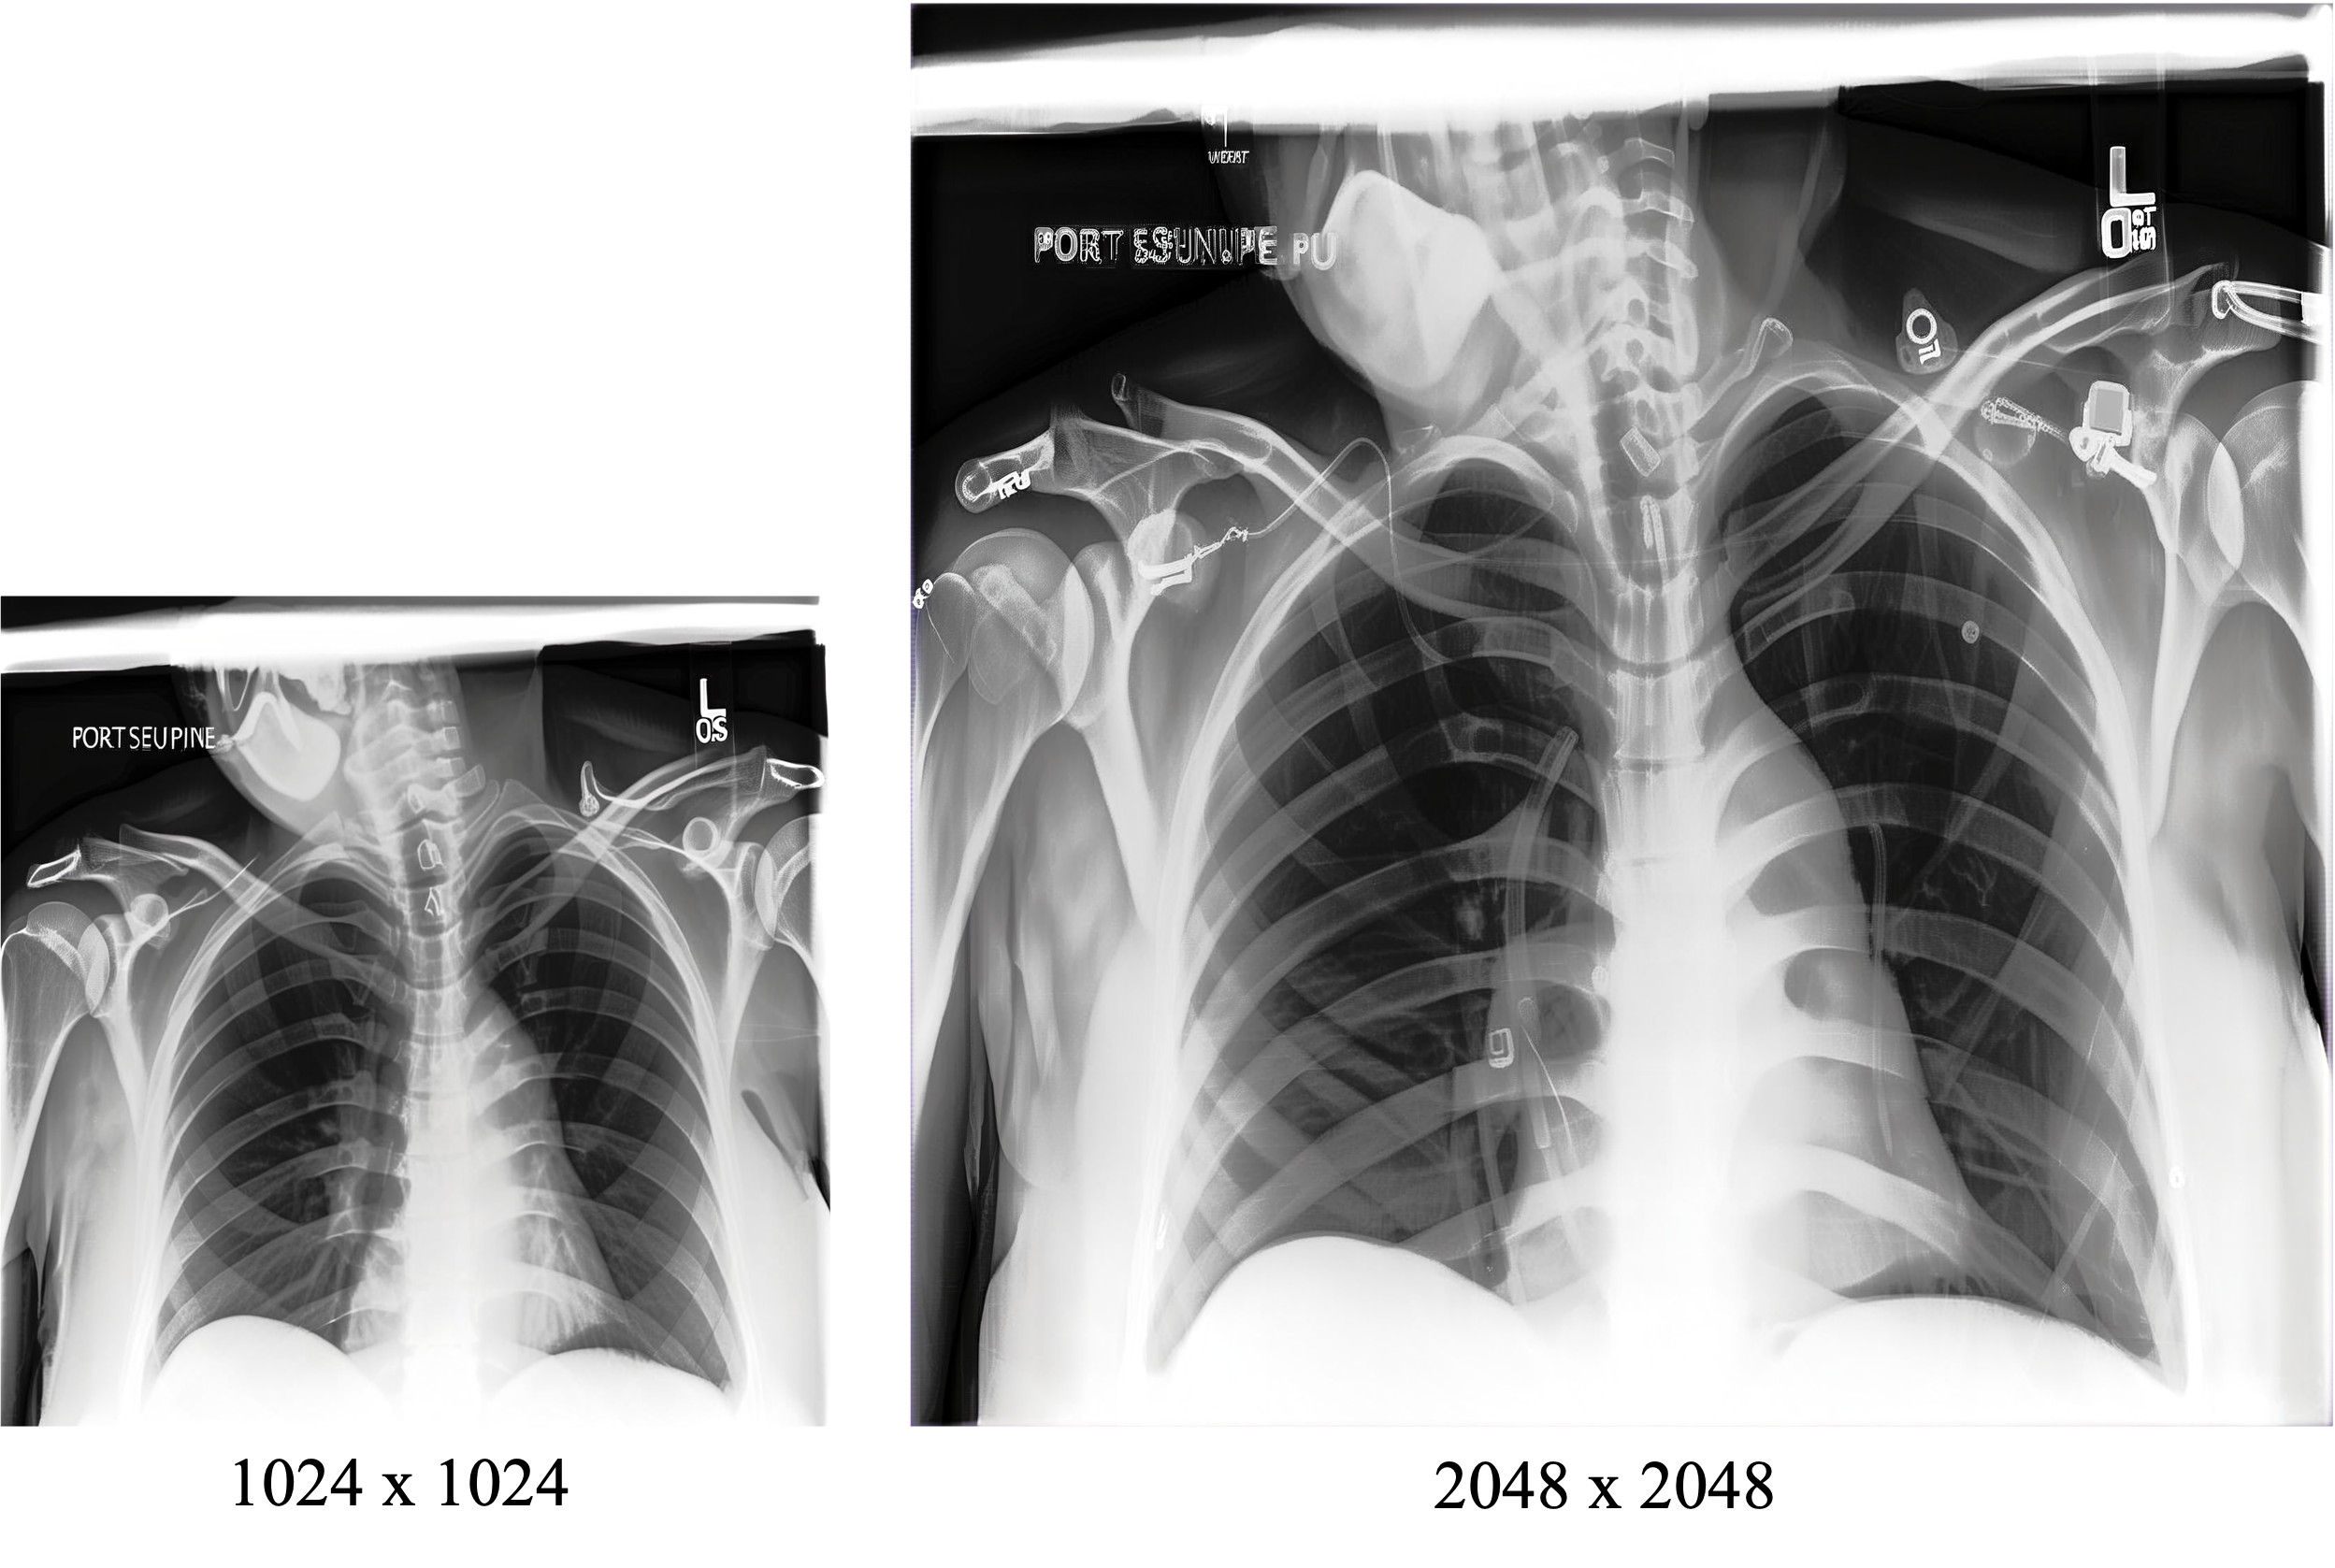

Qualitative Evaluations We present qualitative results of our method under two scenarios: (i) ultra-high resolution generation, showcasing the model’s ability to synthesize anatomically coherent and visually detailed medical images at 1024×10241024\times 1024 resolutions; and (ii) progressive upscaling, illustrating the refinement of semantic and structural details across successive resolution stages of 2048×20482048\times 2048 pixels.

Figure 5: Progressively scaling an image from 1024×10241024\times 1024 to 2048×20482048\times 2048.